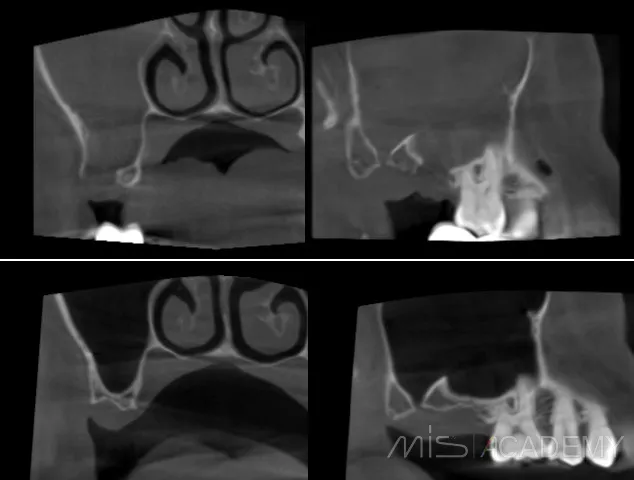

а зона соустья просто попала в кадр. Оказалось, что костный дефект самостоятельно закрылся и теперь там шикарные условия для ОСЛ. Ни разу не видел, чтобы соустья так закрывались. Что ж, будем теперь делать ОСЛ ..